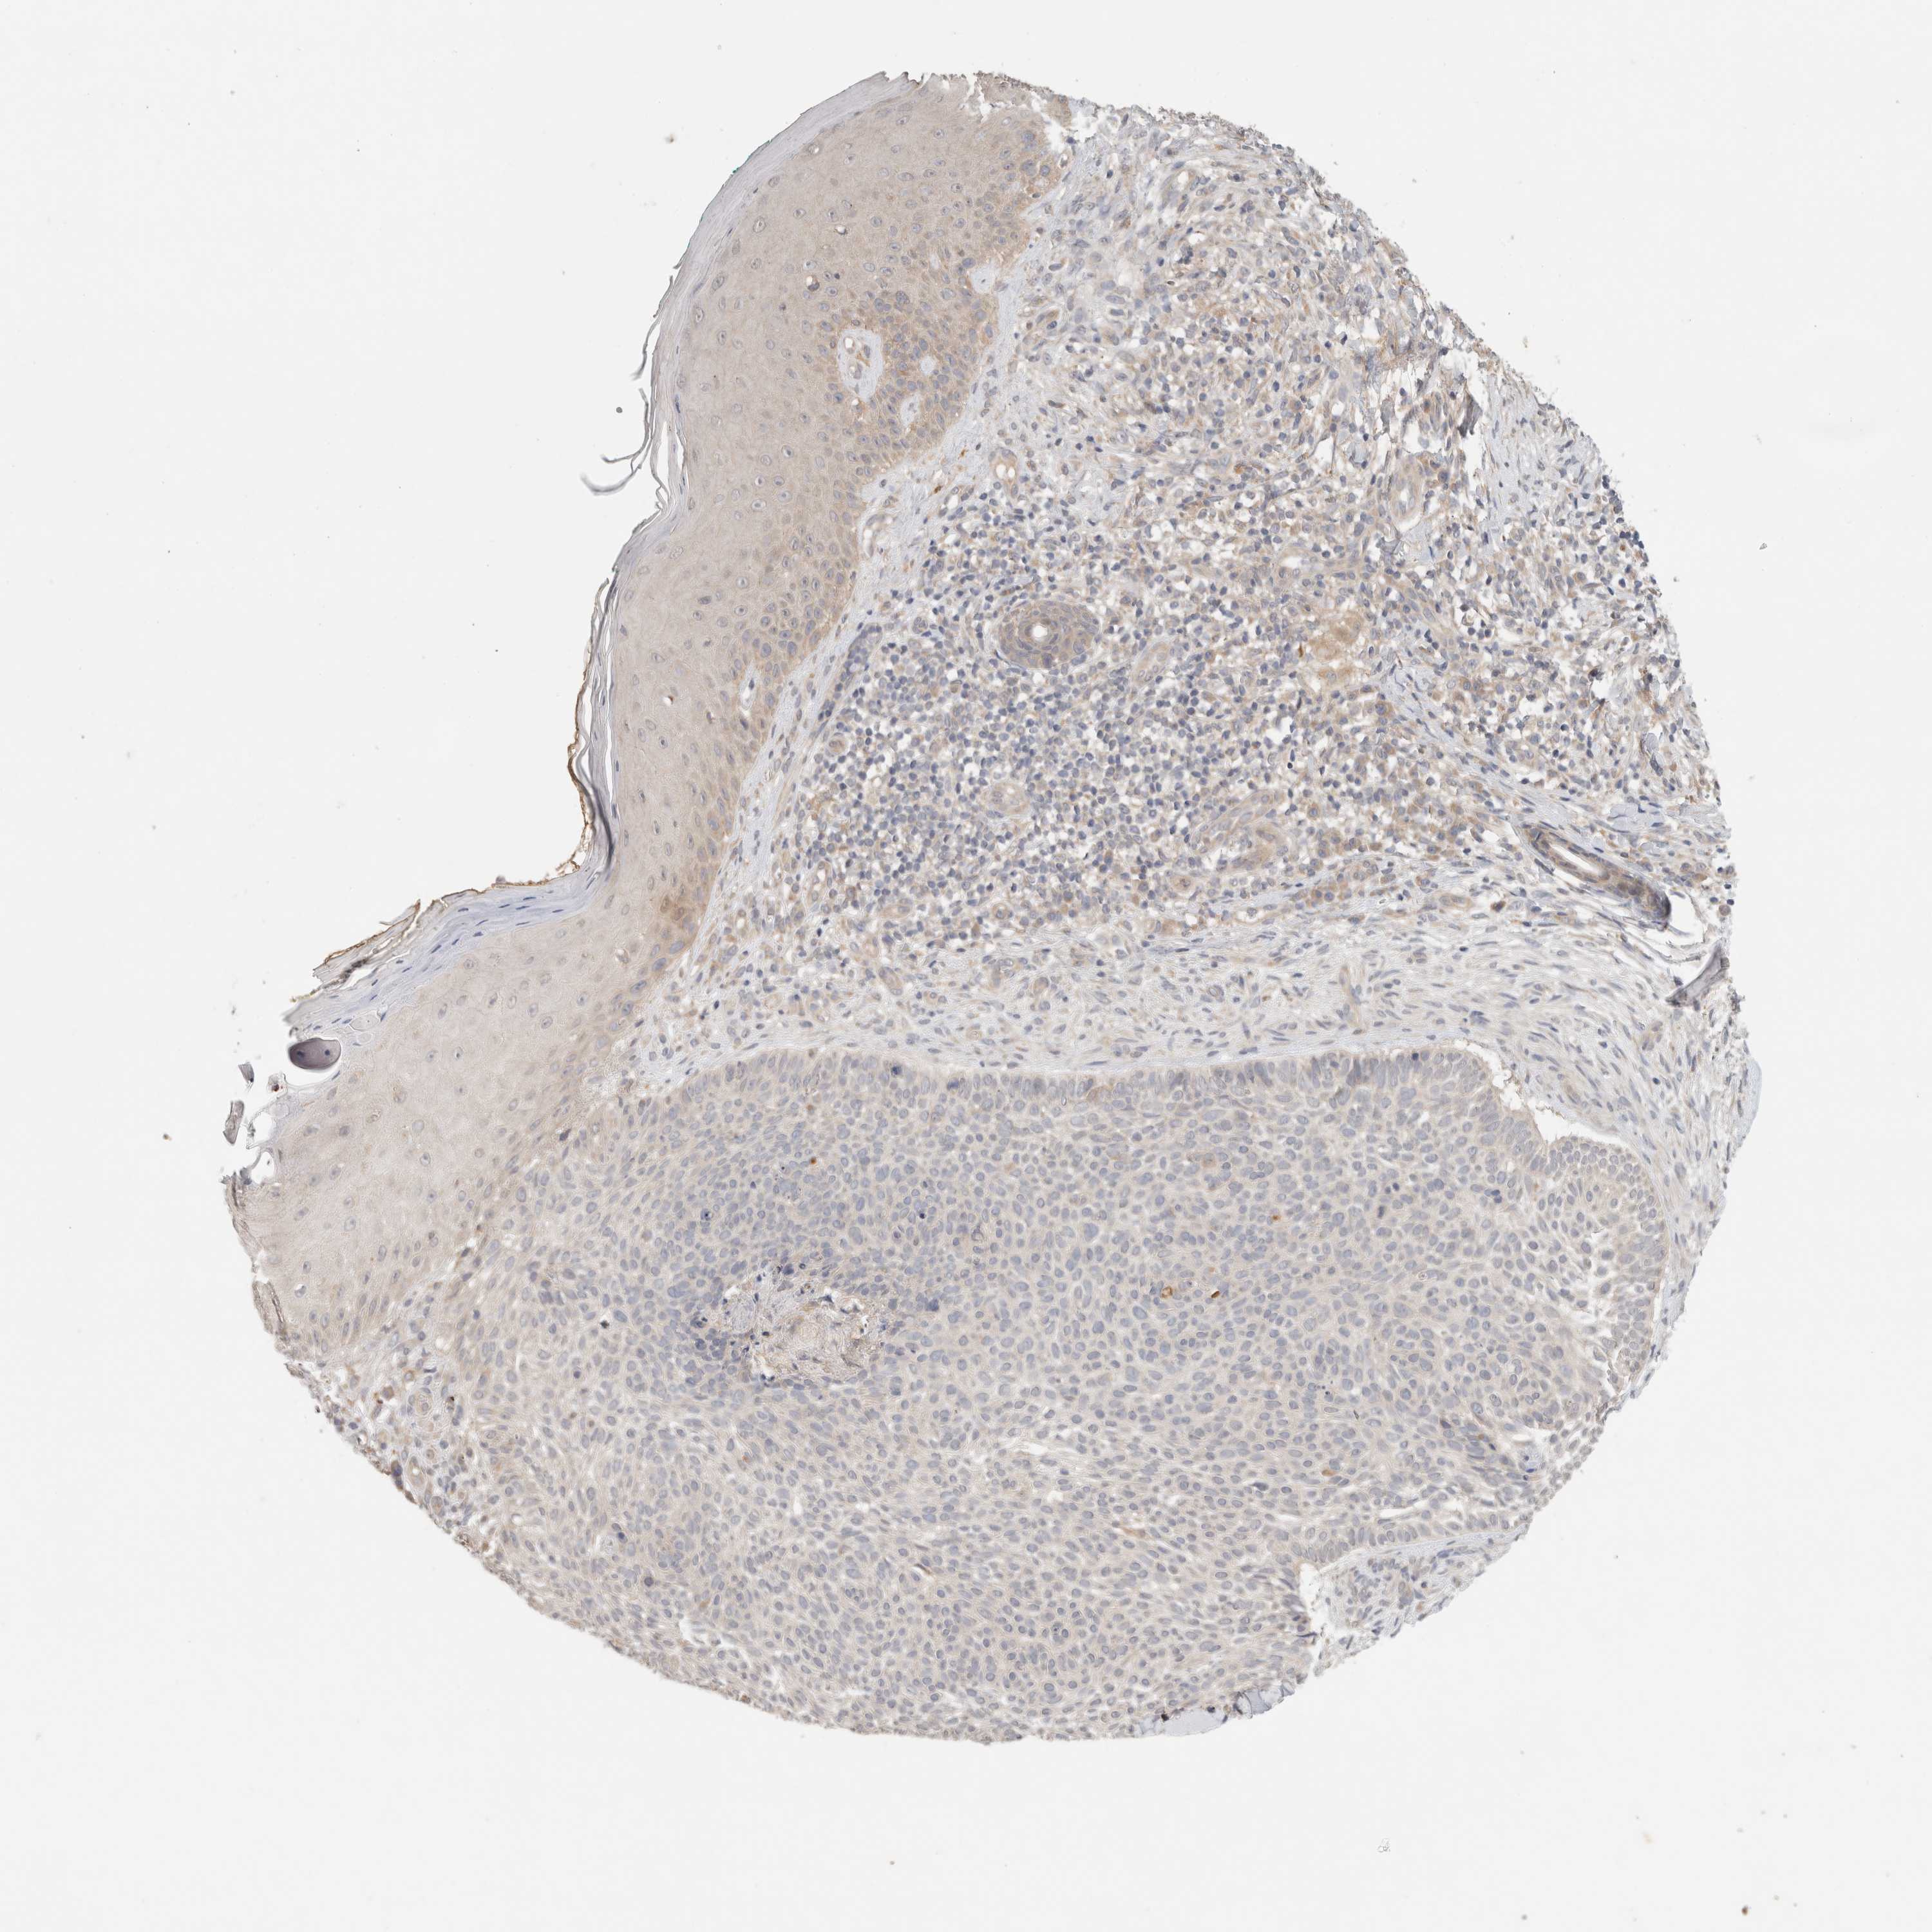

CANCER SKIN CANCER Show tissue menu

Basal cell and squamous cell cancer

SKIN CANCER - Protein expressioni

A mouse-over function shows sample information and annotation data. Click on an image to view it in a full screen mode. Samples can be filtered based on level of antibody staining by selecting one or several of the following categories: high, medium, low and not detected. The assay and annotation is described here.

Each image is clickable and will lead to virtual microscopy that enables deeper exploration of all samples and also displays staining intensity scores, fraction scores and subcellular localization as well as patient and tissue information for each sample.

Antibody CAB025148

Staining

Medium

Intensity

Moderate

Quantity

75%-25%

Location

Cytoplasmic/membranous,nuclear

Basal cell carcinoma

Squamous cell carcinoma, NOS

Squamous cell carcinoma, metastatic, NOS